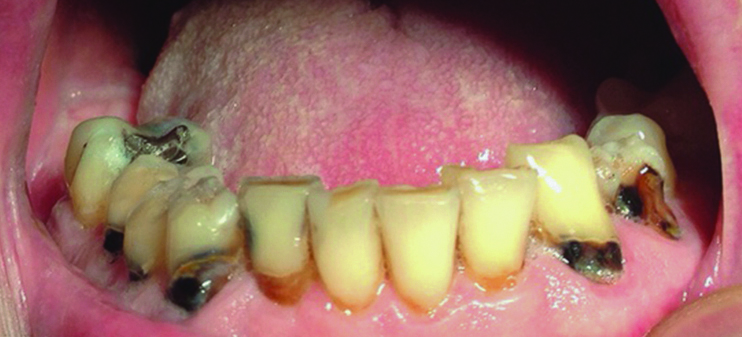

Dental caries, both new and recurrent, is also a frequently occurring infection resulting from lack of saliva. Older adults are particularly vulnerable because many have a greater number of retained natural teeth, previously restored dental surfaces, and gingival recession.11 Recurrent carious lesions are seen particularly in the buccal surfaces of previously restored anterior teeth and in incisal margins4 (Figure 1). Without proper salivary flow to restore the oral pH levels and to regulate bacterial populations, the oral cavity is rapidly colonized with caries-associated microorganisms.11 In regard to periodontal disease, the evidence in the literature is conflicting as to whether individuals with xerostomia are at an increased risk for periodontal disease. Some studies26-31 showed that the periodontal condition of individuals with Sjögren’s syndrome is similar to control individuals, whereas others demonstrated that these patients may have a worse periodontal condition compared to controls.32-34 These studies attributed the poorer periodontal conditions observed in individuals with xerostomia to the decrease in the amount of saliva and, consequently, the increase in plaque.35

Fig 1. Patient with rampant buccal/cervical caries due to long-term use of anticholinergic drugs.

Figure 1